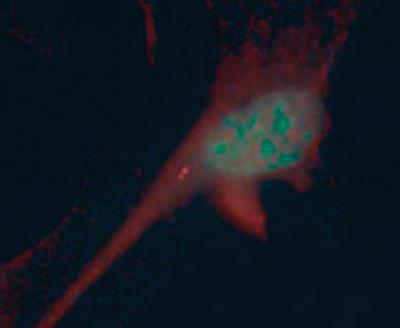

Cilia, tail-like projections found on the surface of cells, are perhaps best known as molecular flippers that help cells move around. Recently, researchers like Nico Katsanis, Ph.D., associate professor at Johns Hopkins’ McKusick-Nathans Institute of Genetic Medicine, have found that cilia are important for many other biological processes, including three of our five senses: vision, hearing, and smell (ciliopathies are often characterized by loss or deficiency in these senses). “That leaves two unexplored possibilities,” says Katsanis. “Taste and touch; we tried touch.”